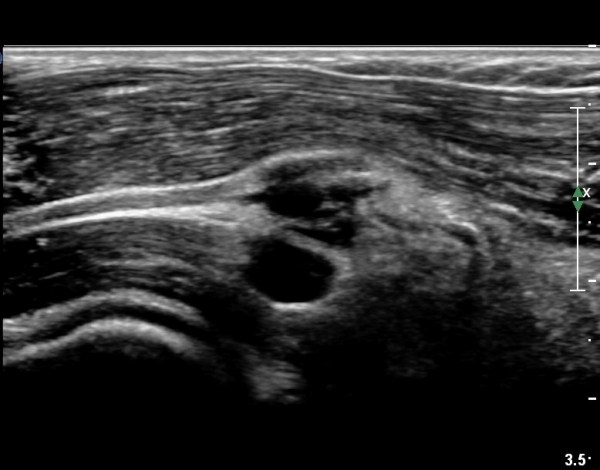

ÃÊÀ½ÆÄ °Ë»ç

¿ä°ñµÎ ±ÙÀ§ºÎ Ⱦ´Ü¸é°Ë»ç»ó Èİñ°£ ½Å°æ ³»ÃøÀ¸·Î ÀÛÀº ³¶Á¾ÀÌ °üÂûµÈ´Ù(»çÁø 1).